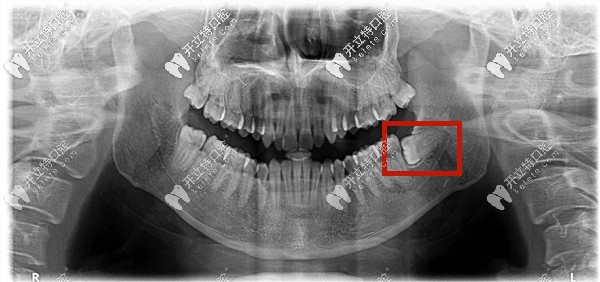

什么是低位阻生齒——就是下頜的阻生智齒的牙冠部位低于前面牙齒的牙頸部以下。

低位水平阻生齒圖片

低位阻生智齒有可能造成前面相鄰牙齒的牙周病、齲病或者是牙根的吸收;

所以如果阻生智齒已經(jīng)頂?shù)角懊娴难例X,有發(fā)炎,食物塞牙的癥狀等是需要拔牙的;

如果沒有以上癥狀,也沒有冠周炎癥發(fā)生,可以考慮保留喲!

下頜低位阻生智齒圖片

低位阻生智齒不是很容易拔掉,難點是暴露牙很少,操作空間有限,不過對于經(jīng)驗豐富的醫(yī)生很容易,加上麻醉的作用,也不是很危險,很疼。

低位阻生齒——就是牙的高處部位低于第二磨牙的牙頸部,它可以是近中低位,垂直低位,遠(yuǎn)中低位等,也有可能牙全部被包埋在牙骨內(nèi),所以又稱之為骨埋伏阻生智齒。

這種情況下的智齒一般從口中看不到,需要拍片才能確定。